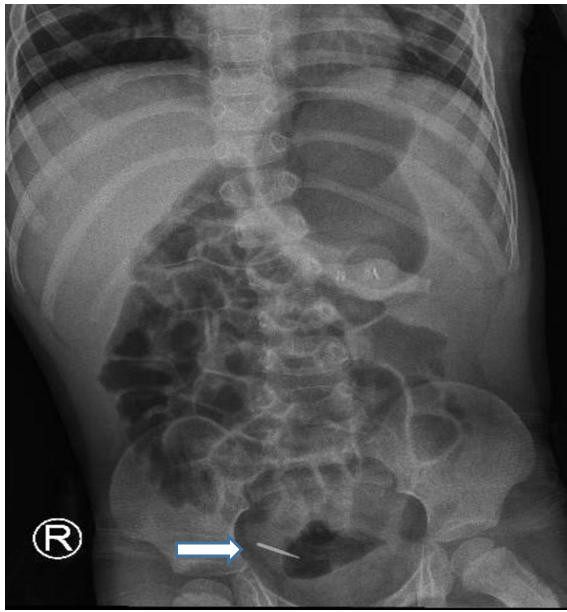

A follow-up chest X-ray, performed one day prior to the scheduled surgery, unexpectedly showed the FB in the stomach. As explained by the mother that the child had an episode of cough, six hours later, another X-ray revealed the FB in the distal small bowel. The patient's mother was instructed to observe his stools for passage of the FB. Two hours after the last X-ray, the FB was passed uneventfully with the stool.

Figure 4: X-ray after 6 hours showed foreign body in the distal small bowel.